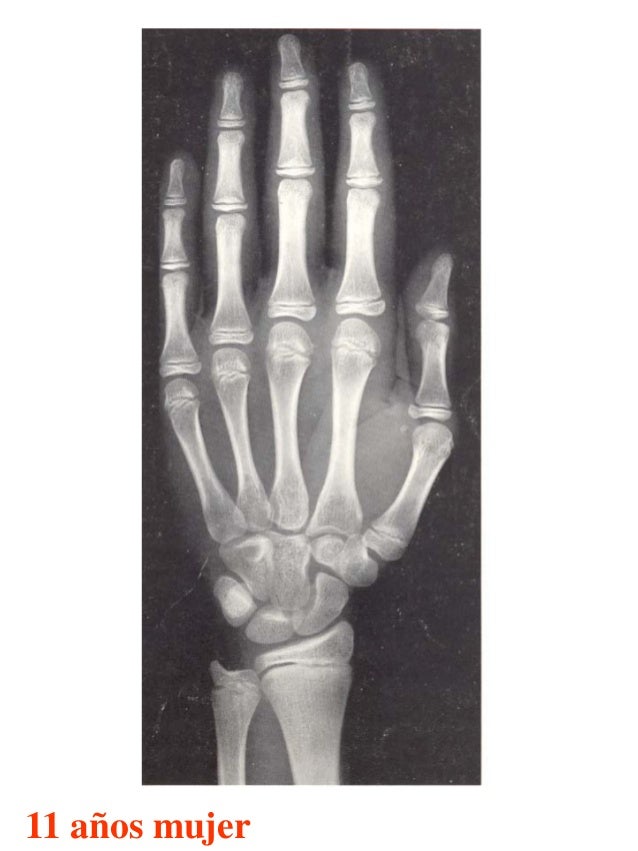

Figura 2 Imágenes de radiografías de mano y muñeca izquierda del

Figura 2 Imágenes de radiografías de mano y muñeca izquierda del Tablas De Greulich Y Pyle Edad Osea The greulich and pyle atlas is used to estimate the age of children and adolescents. El método de greulich y pyle(1) es un método simple de valoración de la edad ósea en pacientes pediátricos. El diagnóstico y la clasificación se basan en el examen físico, el análisis del crecimiento, la maduración ósea, la ecografía de útero y gónadas, y los. Tablas De Greulich Y Pyle Edad Osea.